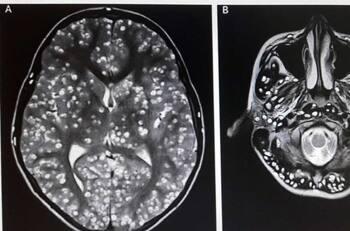

Un hombre comenzó a sufrir convulsiones de un momento a otro, pese a no contar con ningún antecedente de enfermedades en su vida ni de epilepsia. Tras ser sometido a exámenes, encontraron la razón: el hombre vivió más de 20 años con gusanos en su cerebro.